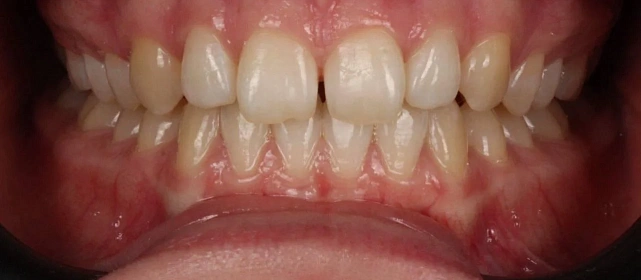

Зубы выровнены, скученность устранена. Установлены несъёмные ретейнеры на обе челюсти, сняты сканы для ретенционных кап. Ортопедия не требуется, рекомендовано лечение у терапевта.

Решение: Установили брекеты на обе челюсти. Расширили дуги, убрали скученность — всё за 15 месяцев. Визиты раз в 4–6 недель для замены дуг. После снятия зафиксировали ретейнеры на обе челюсти, сняли сканы для кап. Ортопед подтвердил, что протезирование не требуется. Терапевт рекомендовал лечение — пациентка записана.

Скученность на обеих челюстях при сужении дуг — классический случай. Зубы здоровые, корни в хорошем состоянии, мотивация у пациентки высокая. Всё это позволило уложиться в 15 месяцев без осложнений. Ортопед подтвердил, что протезирование не нужно. Рекомендовала пройти терапевтическое лечение для полного завершени